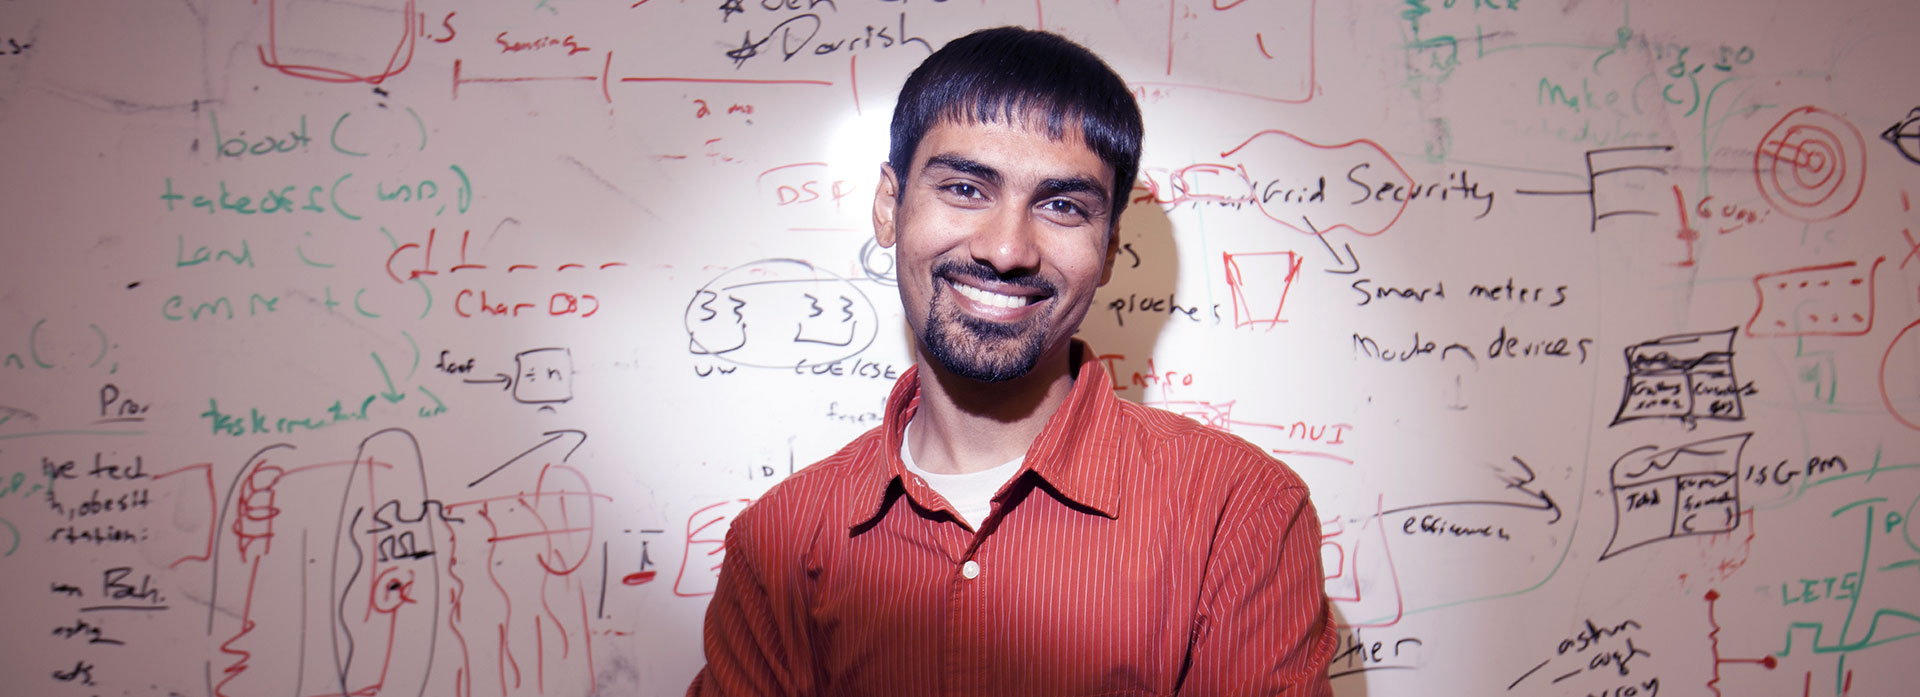

Self-taught AI detects disorders from head scans

This intuitive AI can sort through scans to diagnose stroke, brain haemorrhage, brain tumors and skull fractures.